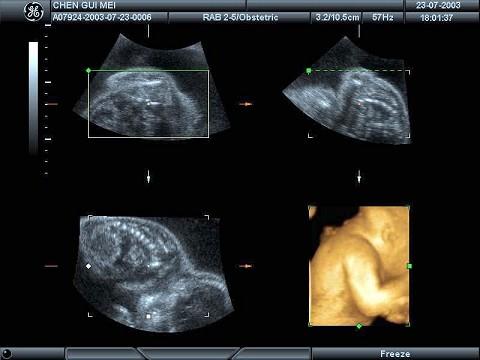

根据胎儿四维成像技术,图中结构为?(?)A.胎儿颜面部B.胎儿上肢及背部C.胎儿臀部D.胎儿下肢E.胎儿胸部

问题 根据胎儿四维成像技术,图中结构为?(?)

选项 A.胎儿颜面部 B.胎儿上肢及背部 C.胎儿臀部 D.胎儿下肢 E.胎儿胸部

答案 B